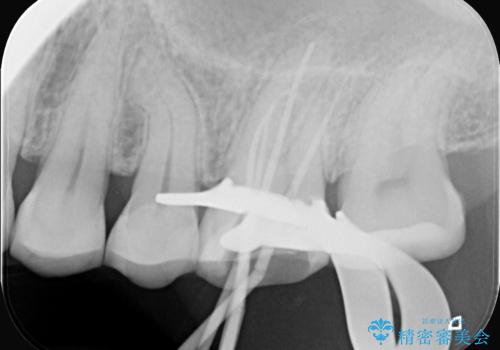

治療はまず、感染源を徹底的に除去する根管治療から開始しました。治療の精度を高めるため、ラバーダムや顕微鏡などを使用し、根管内を丁寧に清掃・消毒。これにより、痛みの原因を根本から取り除きました。